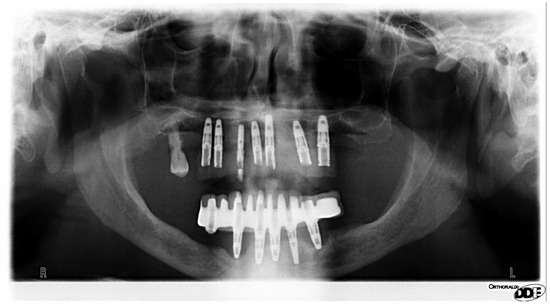

A 78-year-old Caucasian male with primary degenerative dementia (Alzheimer’s disease), who was treated with Memantine, Quetiapine, and Haloperidol sought treatment for difficulty in chewing. The patient complained about other comorbid medical conditions that also required numerous medications, such as, Allopurinol, Simvastatin, baby Aspirin, a mixture of ethyl esters of polyunsaturated fatty acids, and the association between Telmisartan and Hydrochlorothiazide. The patient had a fixed dental prosthesis supported by dental implants, delivered many years before. In recent years, with the increase in difficulty of carrying out oral hygiene procedures, the implants had developed peri-implantitis (Figure 1). The treatment plan was to remove three implants and to retain the others, in order to fabricate a removable denture with implant retention. However, during the dental procedure, it was assumed that the patient swallowed a small screwdriver (Figure 2) due to a sudden unconscious movement. The screwdriver was not tethered to a dental floss, the clinician thought that was not necessary because the procedure involved only the anterior teeth.

Figure 1. A panoramic radiograph showing evident peri-implantitis in lower jaw.